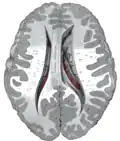

Structure

Along with the putamen, the caudate forms the dorsal striatum, which is considered a single functional structure; anatomically, it is separated by a large white-matter tract, the internal capsule, so it is sometimes also described as two structures—the medial dorsal striatum (the caudate) and the lateral dorsal striatum (the putamen). In this vein, the two are functionally distinct not because of structural differences, but merely because of the topographical distribution of function.